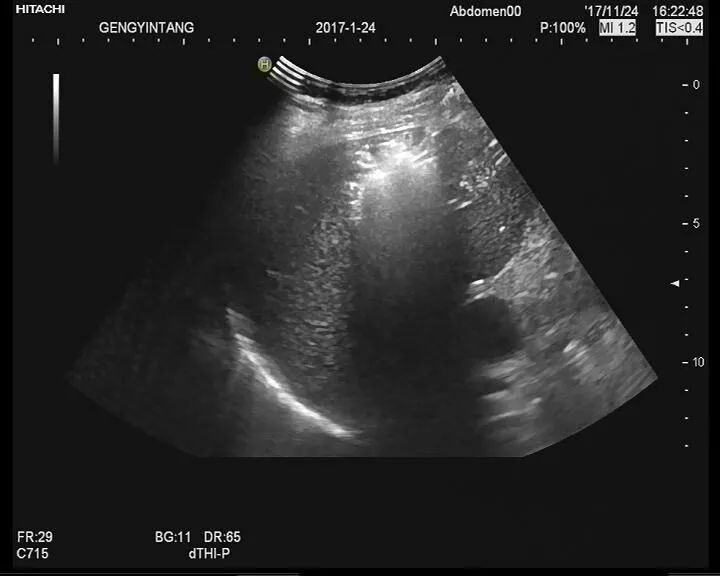

3、镜检

需行乙状结肠镜,可直视诊确诊结肠炎,获取大便或黏液行培养及镜检,并对病变区域进行活检。尽管内镜观察和活检结果不一定可做出诊断,因不同类型结肠炎间表现可有重叠,但急性、自限性、感染性结肠炎,可由组织学上与慢性、特发性UC或CD性结肠炎相鉴别。严重肛周疾病、不累及直肠、无肠道出血以及结肠非对称性或节段性受累多提示克罗恩病,而非溃疡性结肠炎。初期并非必行结肠镜检查,若炎症向近端结肠蔓延,超出乙状结肠镜所及范围,可选择结肠镜检查。